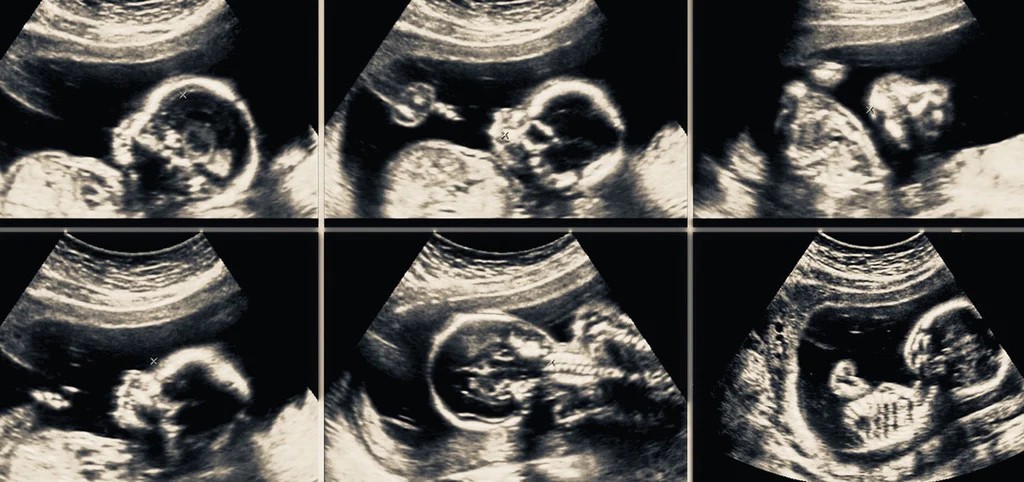

Ultraschall: Darstellung der kindlichen Entwicklung, Erkennung von Fehlbildungen.